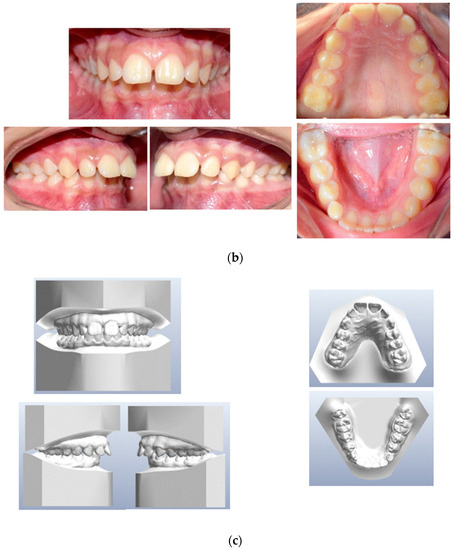

1. Introduction

2.1. Treatment Objectives

- Improve overjet and overbite;

- Achieve bilateral canine and molar class I occlusion;

- Increase facial esthetic balance;

- Level the arches and make both coordinate with each other;

- Orthodontic correction of the impacted lower left canine.